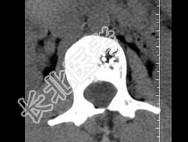

- 单项选择题根据所提供的图像,最可能的诊断 ( )

A、骨结核

B、多发性骨转移

C、骨血管瘤

D、退行性变

E、骨质疏松

- 栅栏样改变是椎体血管瘤的特征性表现,在C